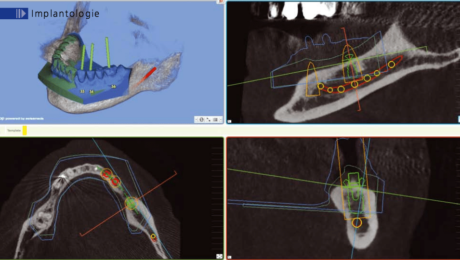

Un cone beam et une prise d’empreinte optique ont été nécessaire pour réaliser la planification implantaire du cas.

Il a été prévu de poser 6 implants au Maxillaire et 4 implants à la mandibule .

2 guides SMOP ont été imprimé, appuis dentaires, muqueux + fixation par clavettes.